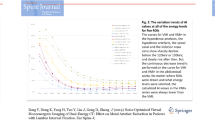

Compared to the positive Hounsfield Unit (HU) of hyperdense artifacts measured on CI (696.04 ± 218.17 HU), the attenuation of artifacts on CIMAR significantly decreased (490.82 ± 181.42 HU, p < 0.001); the attenuation of artifacts on the VMIMAR at 60 – 120 keV were lower than CI, and the differences were significant on the VMIMAR at 80–120 keV (p < 0.001) (Table 1). And the significant difference was detected among the different keV levels of the VMIMAR (p < 0.05). In the VMIMAR series, the attenuation of hyperdense artifacts gradually decreased with increased keV levels; the attenuation of artifacts on VMIMAR 80 keV was significantly lower than CIMAR (469.36 ± 162.21 HU VS 490.82 ± 181.42 HU, p = 0.005). The downtrend showed sharp at 50–70 keV and, relatively flat at 80–120 keV (Fig. 2A).

The trend chart of the attenuation (a), the noise (c) of the vessel and artifact, and the width of artifact (b) in CI, CIMAR, and VMIMAR of various keV levels (50 – 120 keV). The attenuations, widths, and noises of hyperdense artifacts and periprosthetic vessels all gradually decrease with increased keV levels. The similar downtrends all show sharp at 50–70 keV and, relatively flat at 80–120 keV. At 80 keV level, the vascular attenuation is higher than 200 HU which is sufficient vascular opacification, simultaneously, the attenuation of artifacts is also below 500 HU (a). The vascular attenuation gradually drops to 200 HU at 90 keV. And the change of the width of artifacts, the noises of vessels and artifacts tend to be stable and small among the keV levels over 80 compared to the 50–70 keV levels (b–c). The vascular noise on VMIMAR at 50–70 keV was even higher than that on CI (c)

The average width of the hyperdense artifacts on CI was 48.51 ± 16.33 mm, and significantly reduced on CIMAR (28.74 ± 9.9 mm, p < 0.001); the average width of the hyperdense artifacts on VMIMAR was lower than CI, and the differences were significant on the VMIMAR at 70–120 keV (p < 0.001, Table 1). The average width of the hyperdense artifacts gradually decreased with increased keV levels and was significantly lower than CIMAR on VMIMAR 80 keV (26.76 ± 10.37 mm VS 28.74 ± 9.9 mm, p < 0.001), with the lowest occurring on VMIMAR 120 keV (22.41 ± 10.69 mm, p < 0.001). A similar downtrend was observed at the different keV levels. The difference between 50 and 80 keV was about 9 mm, while it was only about 3 mm between 90 and 120 keV (Fig. 2B).

Vascular attenuation

Vascular attenuation was found highest on VMIMAR 50 keV (555.19 ± 141.19 HU) compared to all other reconstructions. Compared to the vascular attenuation measured on the CI (387.26 ± 73.65 HU), the attenuation decreased on CIMAR and VMIMAR at 70–120 keV, and the differences were significant on CIMAR and VMIMAR at 80–120 keV (p < 0.001). In the VMIMAR series, vascular attenuation gradually dropped to 200 HU at 90 keV with increased keV levels (Fig. 2A).

Image noise in vessels and artifacts

Image noise in artifacts was found highest on CI and VMIMAR 50 keV (122.92 ± 53.34, 125.37 ± 64.79, respectively). In the VMIMAR series, image noise in artifacts gradually decreased with increased keV levels. The downtrend was also steep at 50 – 80 keV and, relatively smooth at 90–120 keV. And no significant difference was detected at 100–120 keV (p > 0.655). Image noise in artifacts on VMIMAR 80 keV was lower than CIMAR without significant difference (80.68 ± 32.42 VS 82.08 ± 33.07, p = 0.274) (Table 1, Fig. 2C).

The image noise of the vessel was highest on VMIMAR 50 keV (64.61 ± 50.01), then gradually decreased with the increased keV levels. The vascular noise on CIMAR and VMIMAR at 50–70 keV was even higher than that on CI (37.42 ± 18.57). Compared to vascular noise on CIMAR (45.34 ± 27.78), vascular noise was lower on VMIMAR at 70–120 keV, and the differences were significant on VMIMAR at 80–120 keV (p = 0.004). In the VMIMAR series, the downtrend was not obvious at 90–120 keV and without significant difference (p > 0.815) (Table 1, Fig. 2C).